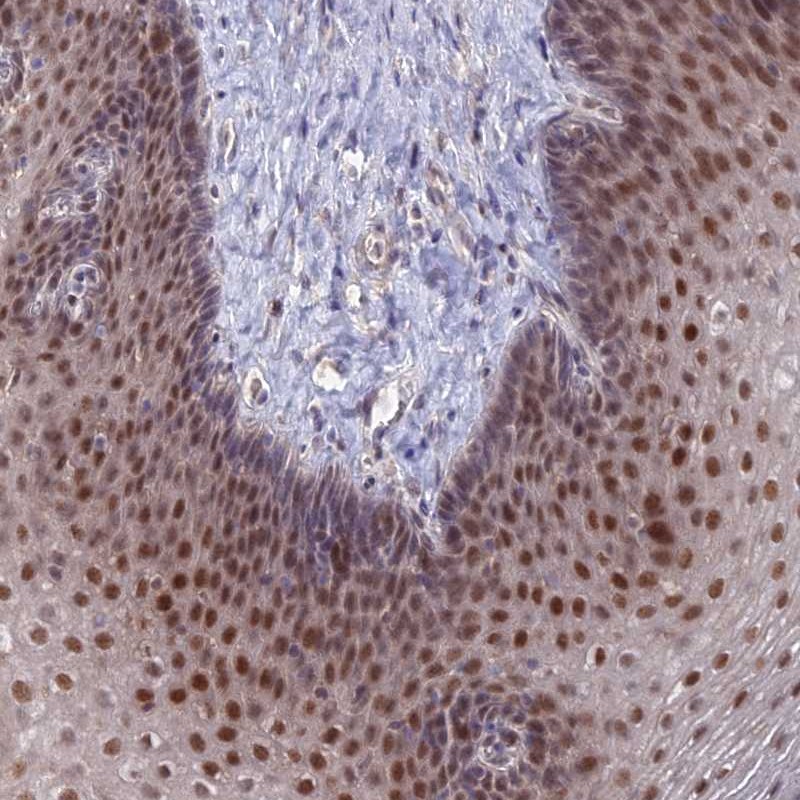

Immunohistochemical staining of human esophagus shows strong nuclear positivity in squamous epithelial cells.